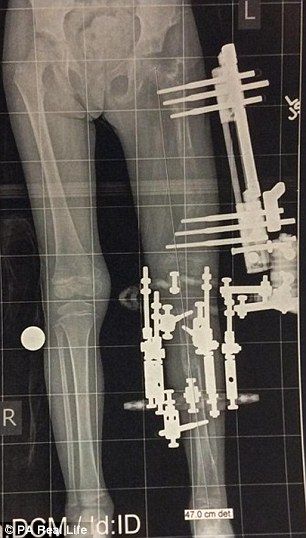

Contactó con el doctor Shawn, experto en discapacidades de este tipo, y decidieron someter a la menor a una complicada operación para alargar su pierna. Tras seis largas horas en quirófano, los médicos pudieron dar la noticia: habían conseguido reconstruir la cadera, el tobillo y la rodilla.

Así, Elsie consiguió andar con 21 meses, pero lo más duro vendría aún. Después de la cirugía, su madre se comprometió a activar manualmente los tornillos de la prótesis que le colocaron para separar el fémur y la tibia tres veces al día. Por tanto, fracturaron la pierna izquierda de la pequeña Elsie 300 veces a lo largo de cuatro meses, y consiguieron lo que pretendían, que la pierna corta se alargase 10 centímetros.